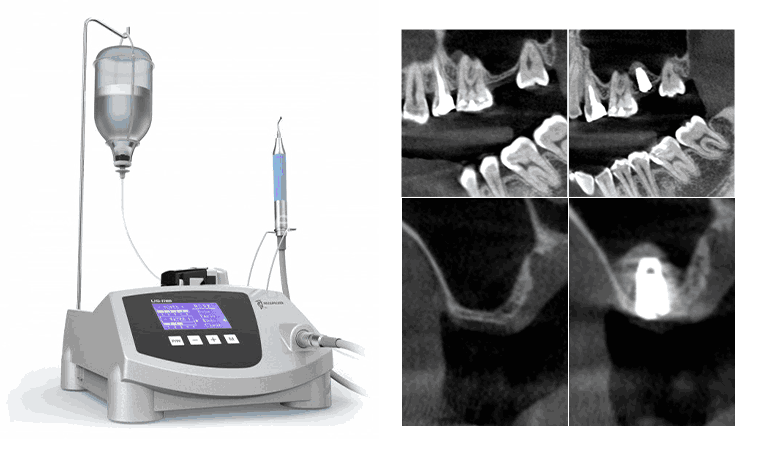

초음파 원리에 의해 고압의 셀라인 주수와 초음파 공명작용으로

뼈만 절삭이 되고 버(bur)나 디스크 등의 회전기구에 일어나는

신경손상, 상악동 막 천공, 큰 혈관 터짐, 크고 작은 출혈, 입술 열상

등 여러 응급 상황을 방지할 수 있습니다. 수술 후 부종이나 멍, 동통

유발을 최소화시킵니다.